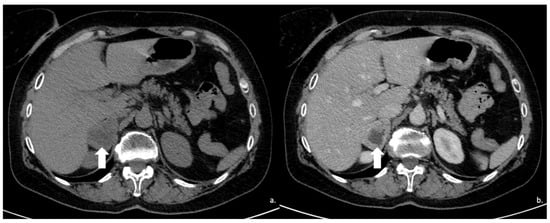

Figure 12.

(a) Unenhanced and (b) venous CT phases show a solid lesion (arrow) in the right adrenal gland with a heterogeneous contrast-enhancement due to necrotic-colliquative phenomena; on histological examination, the lesion was a pheochromocytoma.